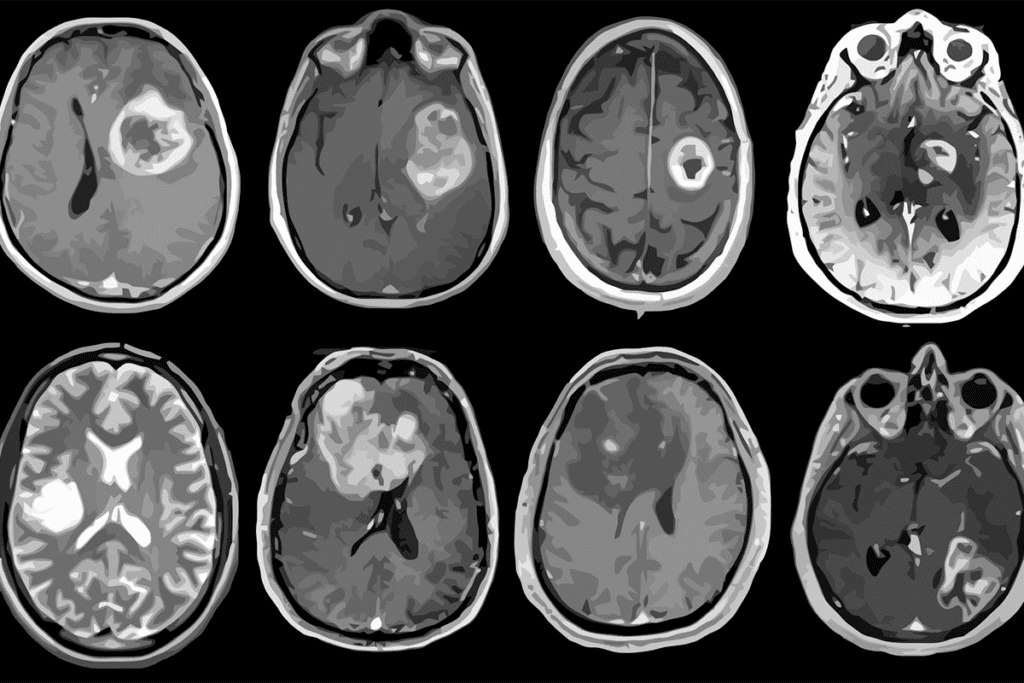

Imaging Tests

Imaging tests are very important for diagnosing brain tumors in kids. The main tests are:

- Magnetic Resonance Imaging (MRI)

- Computed Tomography (CT) scans

- Positron Emission Tomography (PET) scans

These tests help doctors see the tumor, its size, and where it is. They also check how it affects the brain around it.